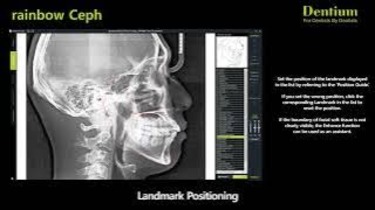

Dentium Rainbow Ceph Software: Demo & Features